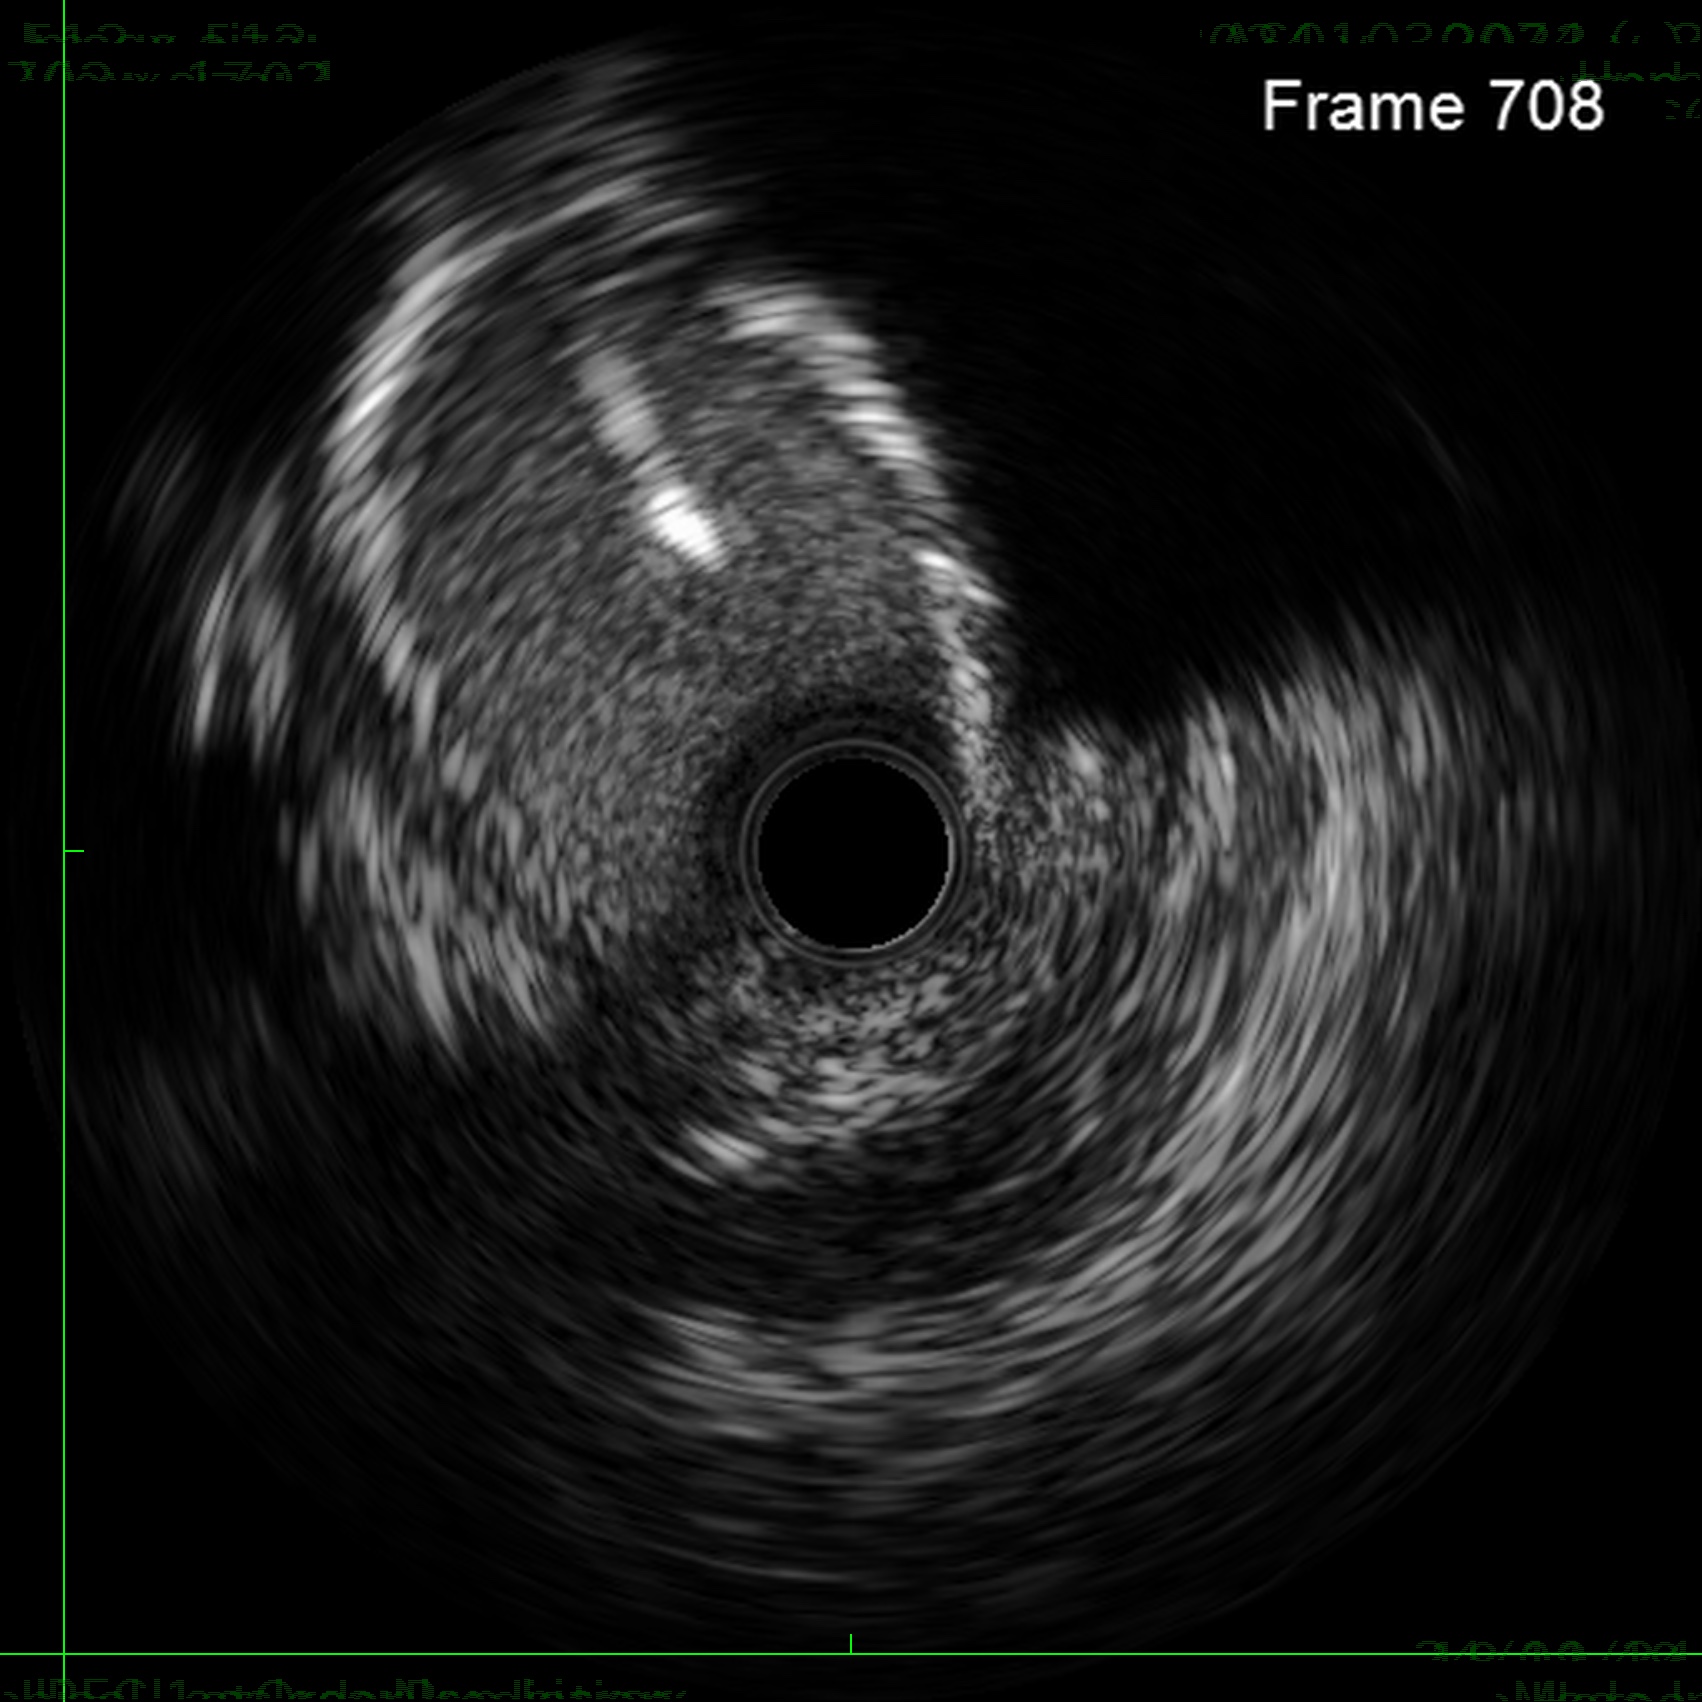

Through bilateral femoral access, 7Fr EBU 3.5 and JR 4.0 catheters were engaged to the left main and RCA. With no antegrade entry, a retrograde marker wire and IVUS-guided antegrade puncture using Gaia Next 2 and Conquest Pro with Finecross failed, as both wires were deflected by the calcified cap despite tip modification with a secondary curve. A retrograde attempt using Gaia Next 2 and 3 with Finecross also failed.Suspecting LAD angulation, an antegrade re-attempt was performed using IVUS-guided puncture with a Conquest Pro 8-20 supported by a Supercross90 under retrograde wire guidance, successfully puncturing the proximal cap. Supercross was exchanged for Finecross, and the wire crossed distally, but Finecross and Corsair Pro XS could not advance due to the tight lesion. After proximal preparation and the anchor balloon technique in the LCx, the microcatheter advanced distally and the wire was exchanged for a workhorse wire. Retrograde injections confirmed true lumen position, and the LAD was predilated. IVUS showed mixed plaque and myocardial bridging in the mid LAD and mixed plaque at the ostial LCx. Further preparation was performed with a 3.5 mm scoring balloon. A hybrid strategy using a 4.0¡¿20 mm DCB for the LCx and a 4.0¡¿32 mm DES from LM to LAD, followed by 5.0 and 4.0 NC balloons for post-dilatation, achieved final TIMI 3 flow without complications.

This case demonstrates a complex left main bifurcation with a blunt ostial LAD CTO and tight ostial LCx stenosis, successfully managed through a hybrid strategy. When both antegrade and retrograde approaches failed, IVUS-guided puncture with a Supercross-supported high–tip-load wire enabled successful revascularization. The angulated microcatheter preserved the wire¡¯s penetration force, allowing puncture of the proximal cap. Procedural safety was enhanced by a retrograde marker and tip injection confirming distal cap position, while intravascular imaging provided the precision required for safe execution and optimal procedural outcomes.